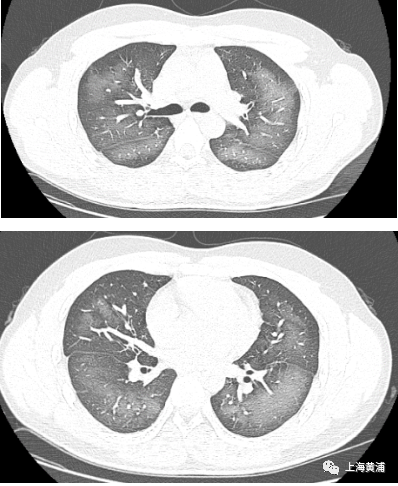

日前,湖南省长沙市一名20岁小伙李林(化名)外出前使用了防晒喷雾,在对着面部喷洒时一不小心误吸,随即出现胸闷、咳嗽的症状。症状一直持续到第二天仍未好转,他急忙来到长沙市第三医院就诊。

经检查,肺部CT片显示,李林双肺赫然呈现大范围白色样病变,报告提示“白肺”。

急诊医生给予李林吸氧、化痰、抗感染治疗后,他的症状得到明显改善。